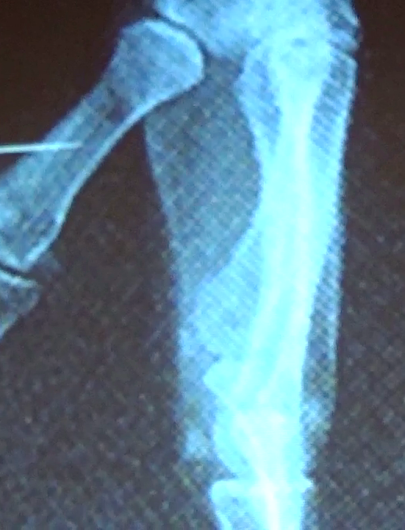

En la imagen de abajo observamos el llamado hueso paratroclear que no es

una fractura por avulsión como se podría pensar en principio sino un defecto

ocasionado por la falta de consolidación del epicóndilo medial